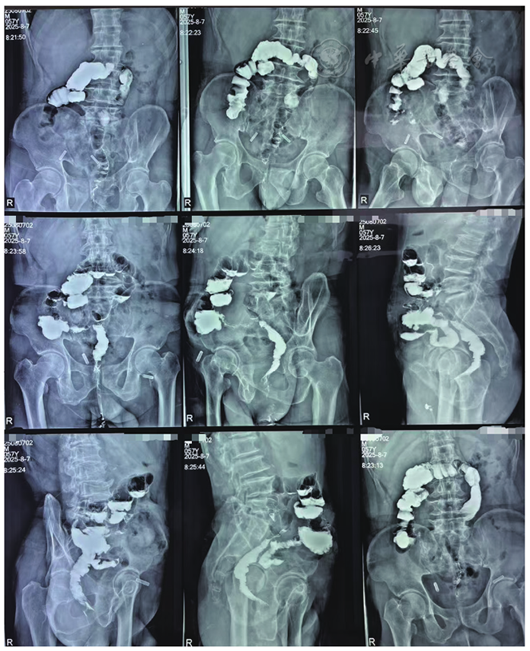

图6 患者术后经肛结肠造影显示术后肠管通畅,无梗阻狭窄